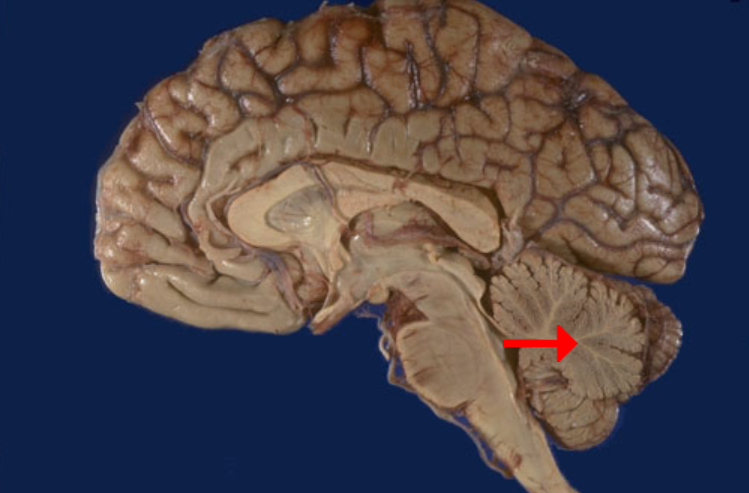

Label this brain part

Frontal lobe

Label this brain part

Parietal lobe

Label this brain part

Occipital lobe

Label this brain part

Thalamus

Label this brain part

Midbrain

Label this brain part

Fourth ventricle

Label this brain part

Medulla

Label this brain part

Corpus callosum

Label this brain part

Mammillary body

Label this brain part

Cerebellum

Label this brain part

Aqueduct of Sylvius

Label this brain part

Tectum (of midbrain)

Label this brain part

Septum pellucidum